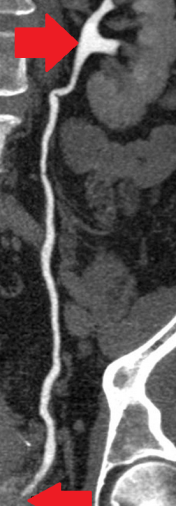

Η αξονική αγγειογραφία αποκάλυψε διάχυτες ασβεστώσεις του αγγειακού τοιχώματος και αθηροσκληρωτικές μεταβολές της κάτω κοιλιακής αορτής και των αμφοτερόπλευρων λαγόνιων αρτηριών, καθώς και έντονη ασβέστωση των μεγάλων και μικρών αρτηριών και των δύο κάτω άκρων. (Ευγενική παραχώρηση Dr. V. Penopoulos).